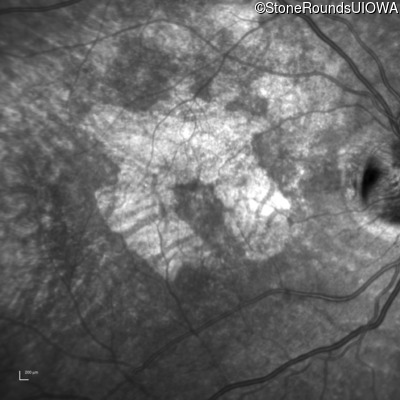

Infrared Fundus Photograph - Left - 20/20 -1

Exemplar